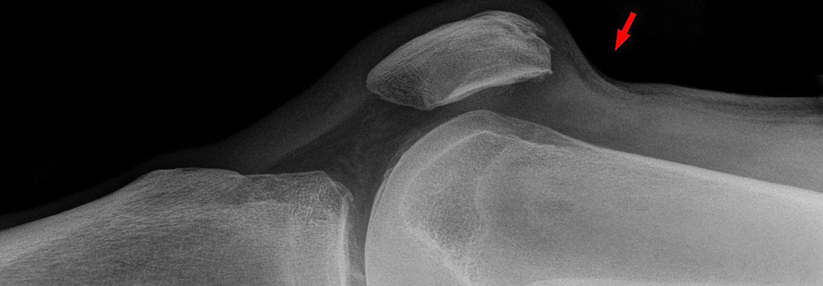

Bei Traumata im Kniegelenk drohen neben Binnenverletzungen und Frakturen auch Rupturen der Quadrizepssehne. So geschehen bei einem Patienten von …